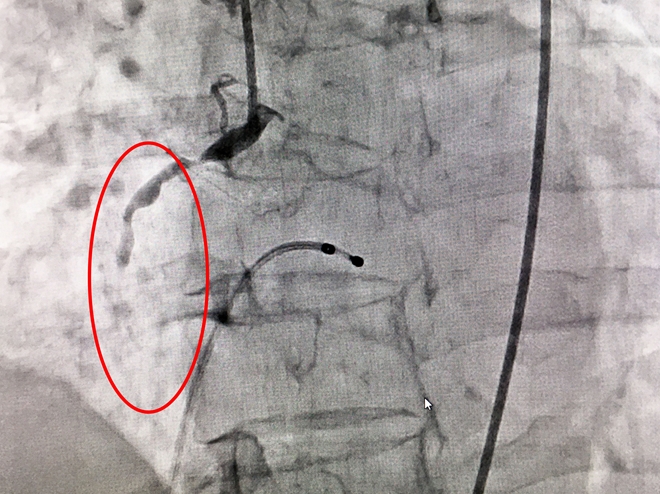

Hình ảnh bệnh nhân bị hẹp nặng mạch vành bên trái và tắc hoàn toàn động mạch vành bên phải tại vị trí xuất phát. |

Trong quá trình can thiệp, hình ảnh chụp cận mạch vành cho thấy, bệnh nhân bị hẹp nặng mạch vành bên trái và tắc hoàn toàn động mạch vành bên phải tại vị trí xuất phát. Ê kip các bác sĩ đã nhanh chóng tiến hành nong động mạch vành và mở thông động mạch vành ở vị trí tắc, khôi phục dòng chảy bình thường.